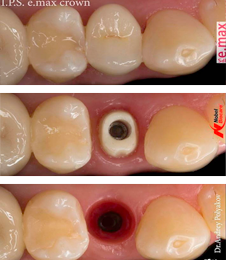

Применяется когда у пациента отсутствует один или несколько зубов. Имплантация проходит в 2 этапа. Сначала устанавливается сам имплант, который полностью срастается с костной тканью за 3-6 месяцев. Затем на него одевается коронка.

Циркониевый абатмент фрезеруется в США при помощи компьютерной 3Д программы PROCERA. PROCERA - самая точная технология, существующая на сегодняшний день, "пионер" в разряде безметалловых конструкций. PROCERA позволяет пациенту получить индивидуальную ортопедическую реставрацию, обладающую биотермическими свойствами и не оказывающую отрицательного влияния на мягкие ткани и весь организм в целом.